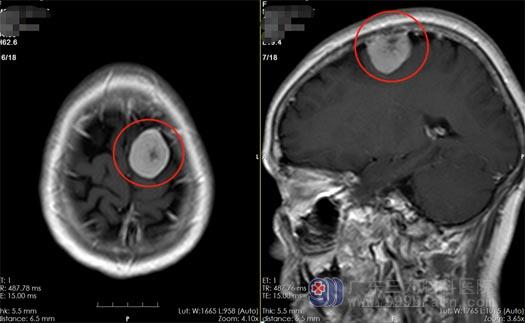

当地医院的头颅CT检查结果提示“左侧顶叶占位性病变,性质待查”,医生建议去上级医院进一步诊治。在广东三九脑科医院神经外五科,曹阿姨做了更详细的检查,头颅MR提示“左侧顶部颅骨内板下占位性病变,大小约为28mmx27mmx26mm,考虑脑膜瘤的可能。”神经外五科的治疗团队一致认为手术是最佳的治疗方案。10月29日,曹阿姨进行了“左侧顶部脑膜瘤切除术”,手术很成功,在显微镜下全切了肿瘤。

▲术前